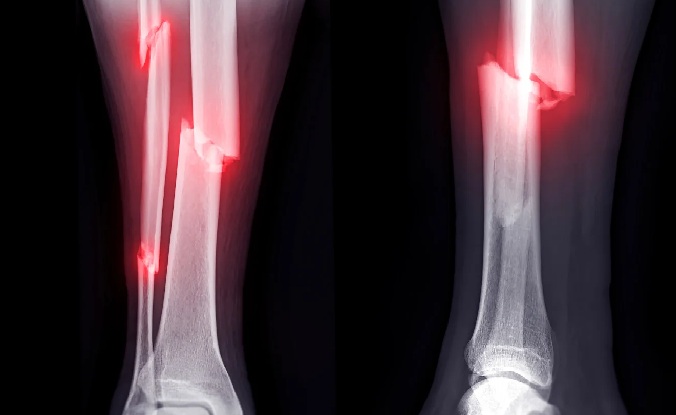

Fracture என்பது எலும்பு முறிவு அல்லது உடைதலை குறிக்கும். ஒரு எலும்பு முழுவதுமாக அல்லது பகுதியளவில் உடைந்தால் அது fracture ஆகும்.

Fracture ஒரு சிறிய முறிவு முதல் கடுமையான பல துண்டுகளாக உடைதல் வரை மாறுபடும்.

X-ray – எலும்பு முறிவு நிலை பார்க்க